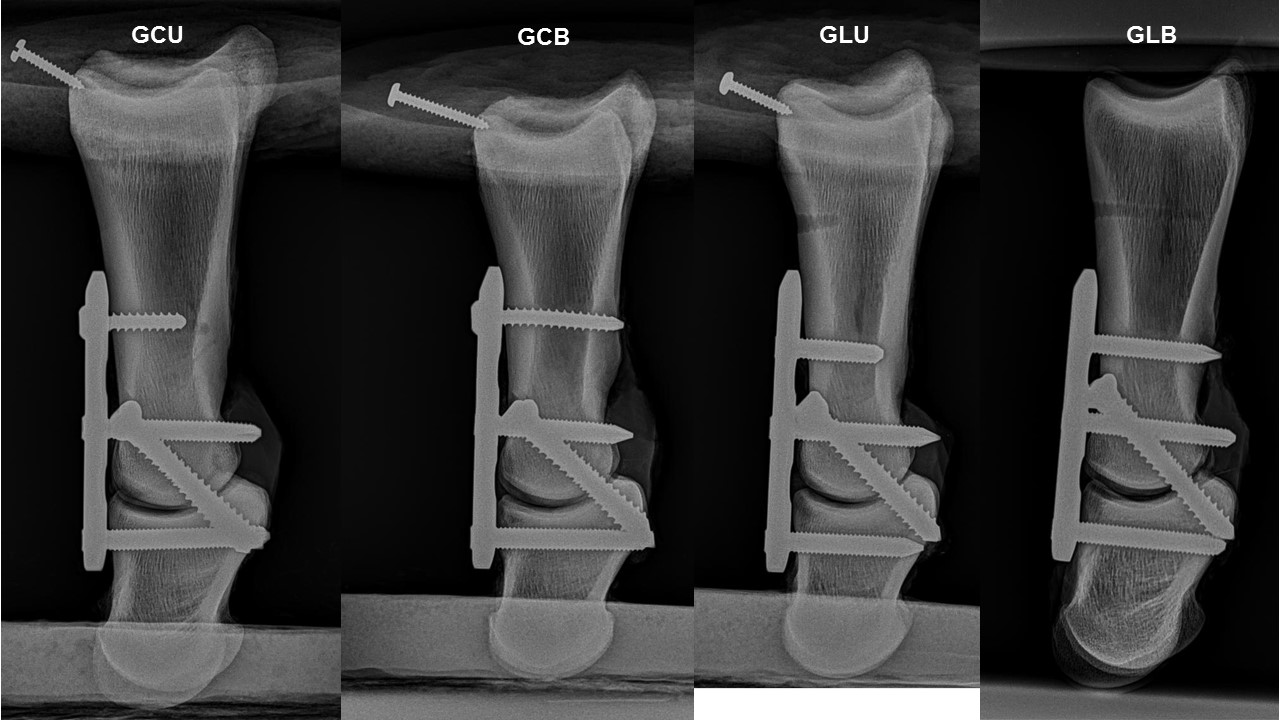

Materials and Methods

PA was performed in 20 cadaveric equine forelimbs, using a 3-hole 4.5mm LCP with two 5.5mmtransarticular cortical screws, divided into four groups according to the type of proximal screw applied to the plate: GCU - cortical screw unicortical; GCB - cortical screw bicortical; GLU -locking screw unicortical; and GLB - locking screw bicortical. A single-cycle axial compression testing to failure was performed. Compression stiffness (N/mm), load (N) and displacement (mm)at peak and apparent elastic limit were measured. Multivariate analysis of variance was used to compare the biomechanical variables between the groups, with the weight of the animals used as a cofactor (MANCOVA), followed by the post hoc Bonferroni test. P-values < 0.05 were considered significant.

There were no significant differences between the biomechanical variables evaluated (P > 0.05).

The type of screw (locking or cortical) applied to the proximal hole of the locking plate and its form of anchorage (uni or bicortical) does not affect the biomechanical properties of equine pastern arthrodesis in cadavers submitted to single-cycle axial compression testing to failure.